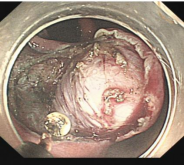

早期胃癌及内镜手术

消化道早癌的病例展示(经内镜手术或活检证实):

胃角的腺癌

胃窦的微小腺癌

胃窦印戒细胞癌

十二指肠降段早癌

胃窦的腺癌 行ESD治疗

术中见较粗穿支血管,裸化后凝除,最终高效、安全的切除病灶。